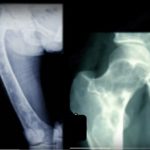

Osteosarcoma

Definition Osteosarcoma is a malignant primary bone tumor defined by the production of osteoid by malignant cells. It is the most common non-hematologic primary malignancy of bone. Incidence Annual incidence is approximately one to three cases per million population. Occurs worldwide with no significant racial predilection. Age Distribution Osteosarcoma can occur at any age. […]